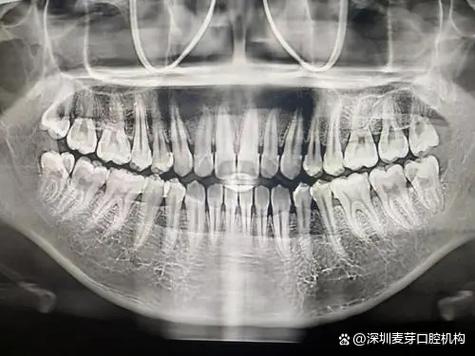

(图片来源网络,侵删)